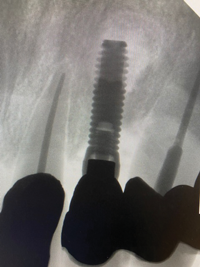

In this case, a dental implant that had been placed 10 years prior was functional, stable, and esthetically acceptable to the patient. However, a significant fistula was present on the facial-apical aspect of the ridge in the maxillary lateral incisor area. This area was painfully sensitive to touch and demonstrated purulence when squeezed. To evaluate the lesion, first, a conventional digital radiograph was acquired, which revealed an apical radiolucency at the apex of the implant (Figure 1). Further analysis using cone-beam computed tomography (CBCT) demonstrated a fistula from that site to the oral environment (Figure 2). Treatment options were discussed, including removal of the implant, followed by grafting, a healing period, and replacement of the implant and implant-retained crown. If this option was selected, a transitional appliance would need to be created. Another option was to attempt to salvage the implant and implant crown by treating the infection and grafting the site to create a new boney wall and eliminate the fistula. Ultimately, the patient accepted this option to attempt to salvage the fixture and crown.

(1.) Preoperative radiographic evaluation demonstrating a large radiolucency at the apical third of the body of an implant fixture replacing the patient’s maxillary left lateral incisor. The implant was stable, and the prosthesis was deemed esthetically acceptable by the patient.

Figure 1

(12.) Immediate postoperative digital radiograph demonstrating the graft material in place.

Figure 12